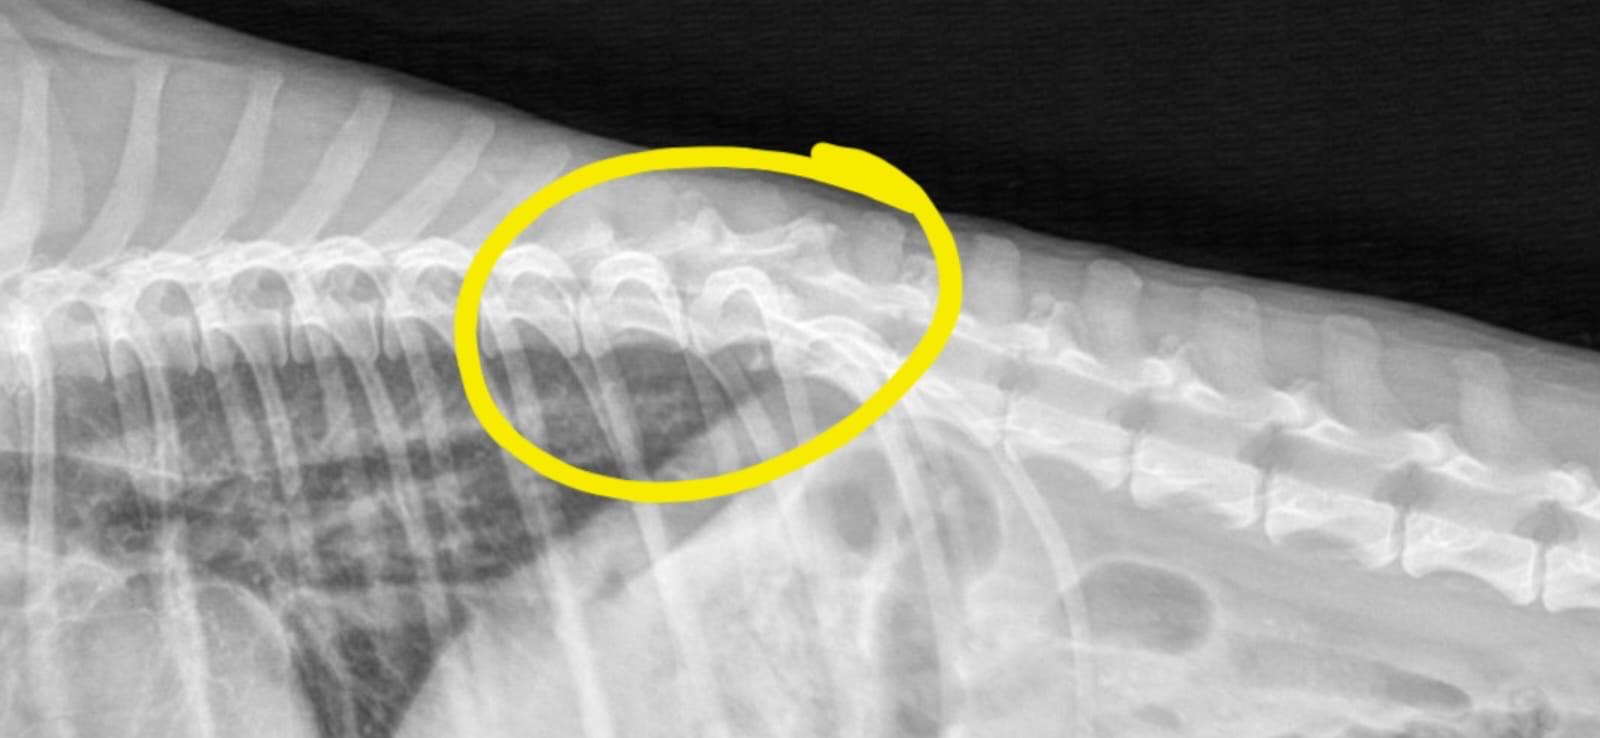

Die tierärztliche Diagnose im September 2025 brachte Klarheit: ein operabler Wirbelkörperbruch (siehe Video). Paloma wurde kostspielig operiert und kämpft sich seitdem tapfer zurück ins Leben. Zwar kann sie aktuell noch nicht ohne Hilfe laufen, doch durch Physiotherapie und der liebevollen Fürsorge ihres Pflegefrauchens macht sie täglich Fortschritte und geht immer besser spazieren (siehe Videos). Paloma kann bereits wieder selbstständig Kot und Urin absetzen, auch Stellreflexe sind vorhanden – vielversprechende Zeichen für ihre weitere Entwicklung, in Richtung Wiederherstellung. Es ist keine weitere Operation notwendig, laut Angaben des spanischen, tierärztlichen Spezialisten.